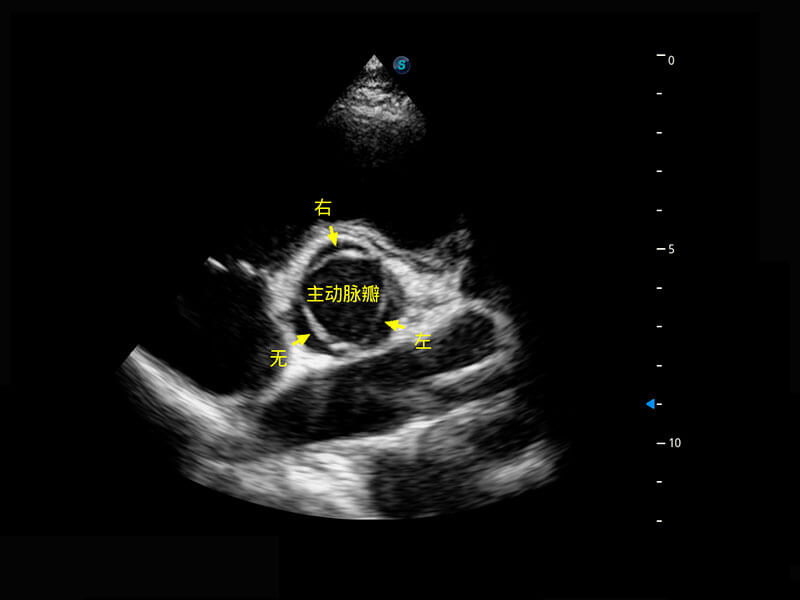

生殖健康

P60优异的图像质量搭载专科探头,在妇科基础疾病的诊断、卵泡生长的监测、输卵管通畅情况的判别等方面为您提供生殖应用方案。

• 腔内妇科-宫腔分离

• 腔内妇科-卵巢

• 腔内三维-宫内节育器

• 腔内三维-光影成像